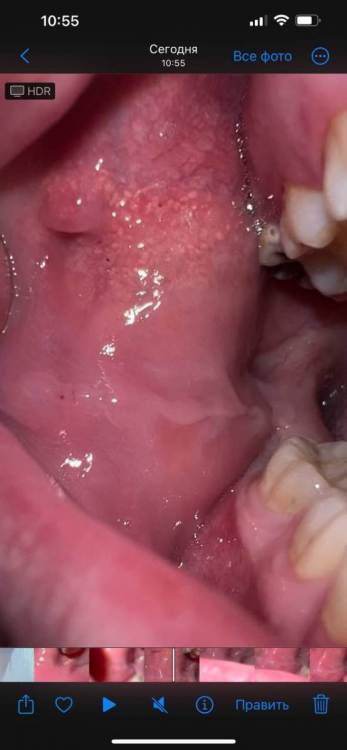

Evgeniy93 Опубликовано 11 марта, 2024 Поделиться Опубликовано 11 марта, 2024 Добрый день! Заметил на щеке белые точки. Есть также небольшой выступ — это образование есть давно, когда были оба зуба мудрости, эта части щеки попадала между двумя зубами и видимо так и осталась. Ничего не болит, но внешний вид смущает. На текущий момент остался верхний зуб мудрости частично разрушенный, который нужно удалить. Не могу точно понять, ровно на том же месте он, что и белые точки, но предполагаю что где-то рядом. Думаю, что виноват зуб, который царапает щеку. Прав ли я или тут что-то более серьезное? Спасибо! Ссылка на комментарий

kramer Опубликовано 11 марта, 2024 Поделиться Опубликовано 11 марта, 2024 Белые точки - это гранулы Фордайса (сальные железы), выступ - выводной проток околоушной слюнной железы 1 1 Ссылка на комментарий